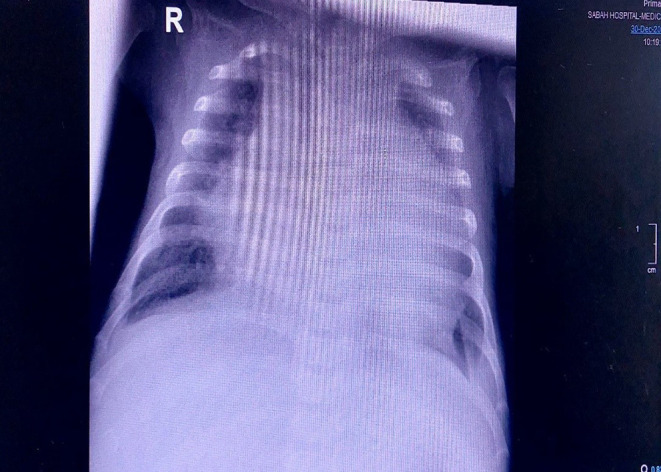

Case presentation: This report describes a 3-month-old female diagnosed with congenital AML, characterized by mixed lineage leukemia (MLL) gene rearrangement. The patient presented with severe complications, including typhlitis, abscess, seizures, and pericardial effusion.